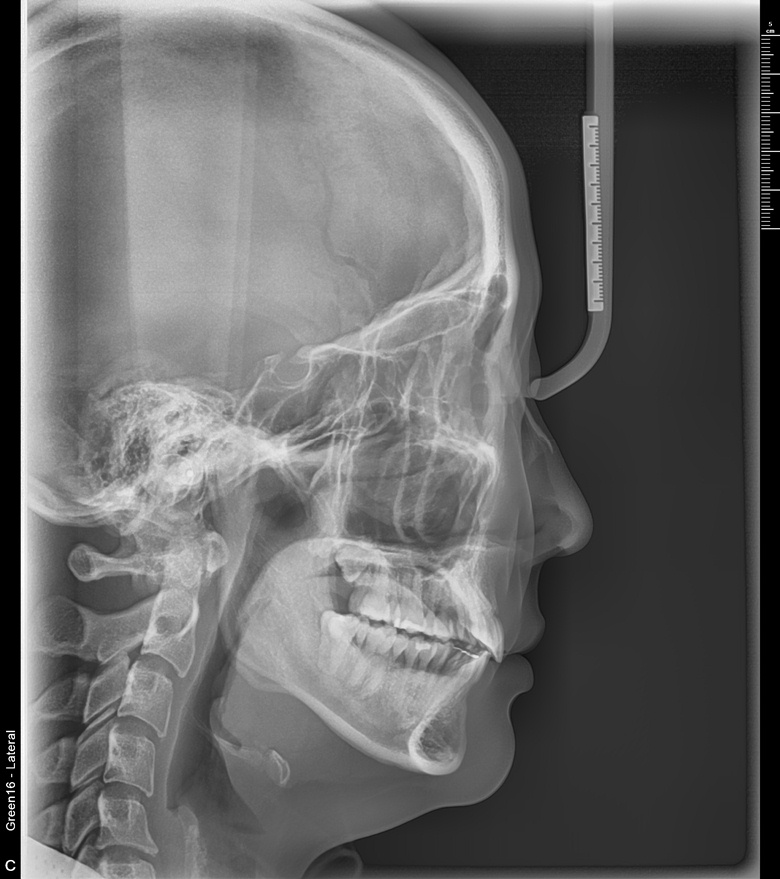

치료 전 사진입니다.